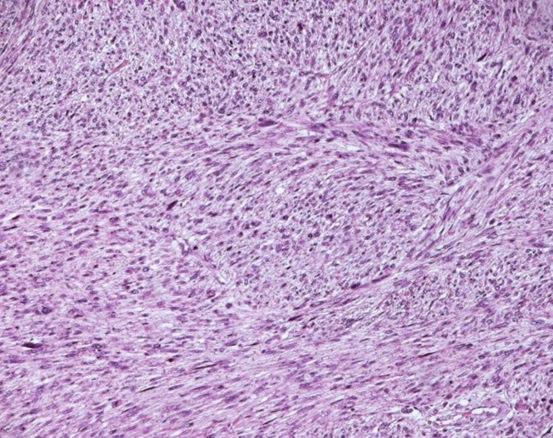

A final histopathology diagnosis of high-grade leiomyosarcoma, (see figure 1), (G3, FNCLCC 1986) pT2b pN0 pM0, AJCC (2002) Stage III, was made based upon immunoreactivity to smooth muscle actin, score 2 (see figure 2). The tumour specimen exhibited negative staining for c-kit and EGFR. Her proliferation index was 90%, which was evaluated thru MIB-1 (Ki-67) (see figure 3). Necrosis was inferior to 50% (score 2) and mitotic index higher than 20 mitoses per field/10 HPF (score 3). The tumour presented, macroscopically, as a bulky, brain-like, white-greyish mass. The tumour was noted to contain diverse necrotic and haemorrhagic areas, and invaded the vesical wall. The size of the mass was 14 cm × 11 cm × 6.5 cm. Histopathology examination of the specimen confirmed that the uterus and adnexa were free from neoplastic invasion. The surgical margins resulted negative at the final examination. LVI was not reported.

Figure 1.

Leiomyosarcoma of the bladder (Hematoxylin and eosin). Reproduced from: [2] under Creative Commons Attribution License